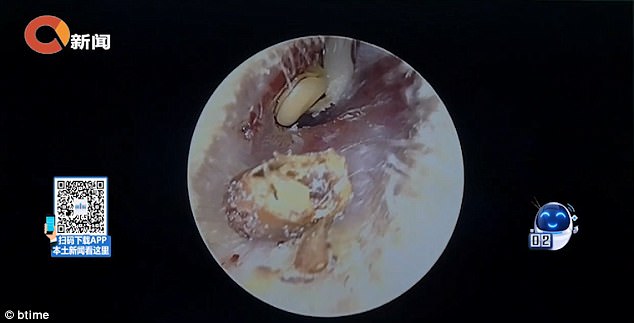

Menurutnya, kacang itu berjaya dikeluarkan selepas pembedahan selama 30 minit.

Dr. Zhang berkata, keadaan suhu di dalam telinga sekitar 37 darjah Celsius dan lembap amat sesuai untuk pembesaran kacang.